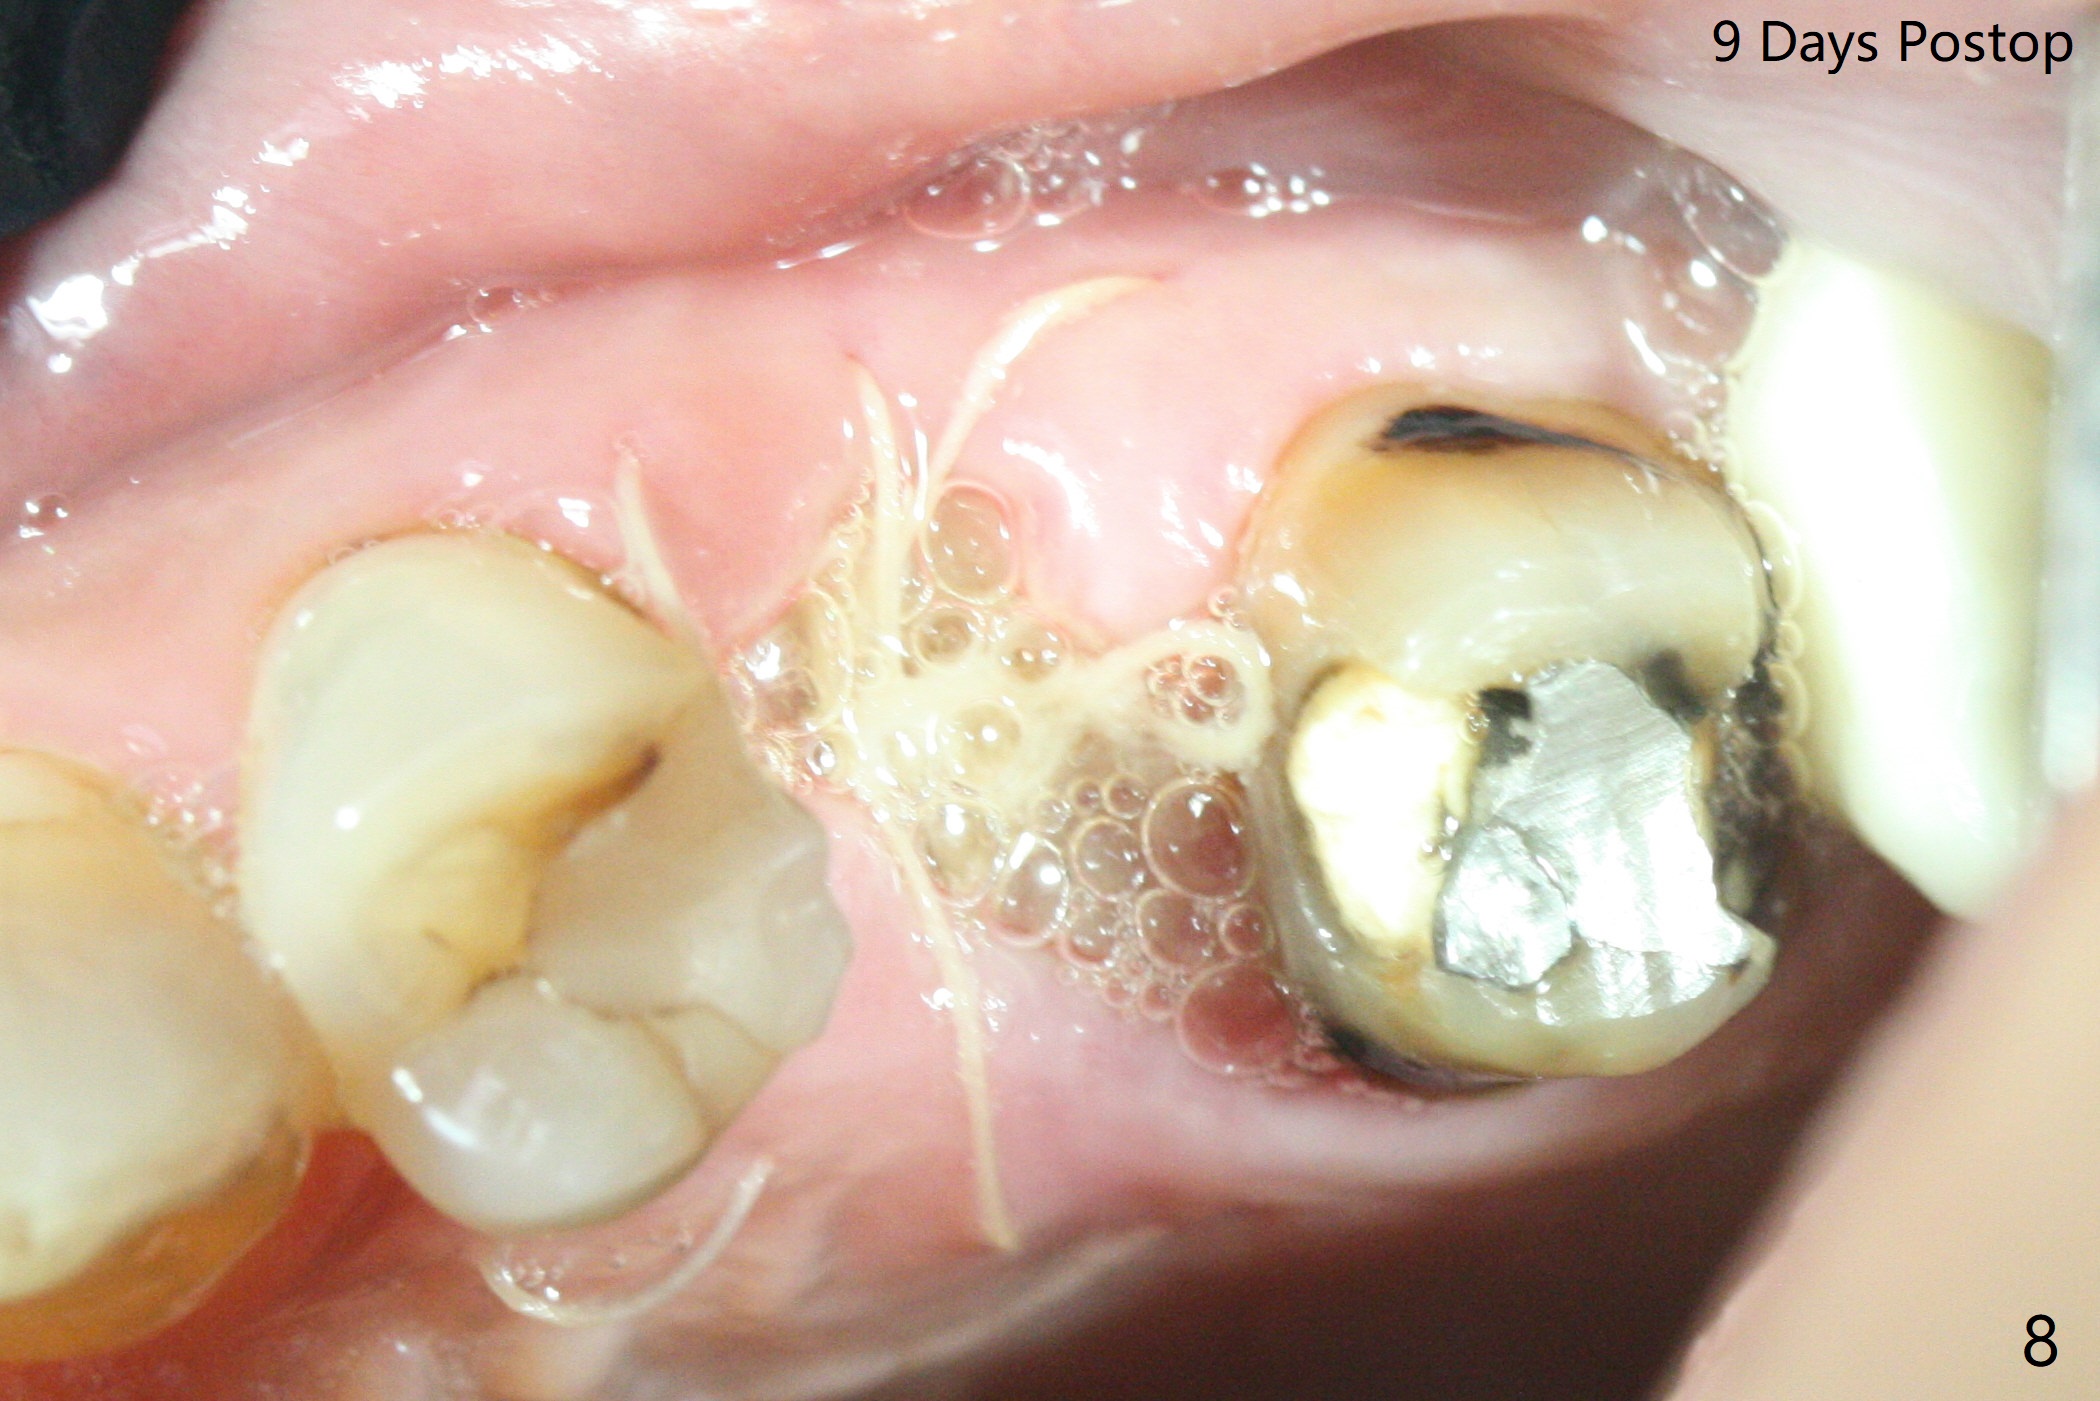

The patient with the anterior cross bite at the left lateral and canine and incipient Class V caries returns to clinic for #13 residual root extraction (Fig.1,2). There is no quality root structure (Fig.2) or space (Fig.3) for socket sheath. Two amalgam carriers of Vanilla is inserted and pushed by the 4x11 mm dummy implant for sinus lift (Fig.4 *). When the same sized final implant (4x11 mm) is placed, a 5.5 mm bone profile drill is used to trim the proximal crests (Fig.5 * sticky bone packed in the buccal and palatal gaps). In fact the implant turns when a 4.5x4(3) mm pair abutment is tightened. The implant is backed up; with a healing screw, sticky bone is placed (Fig.6 *) and then covered with a piece of PRF and a part of GEM cap. The wound is sutured with 4-0 PGA; periodontal dressing is applied. The implant is somewhat over-seated without the bone graft covering the apical end of the implant (Fig.7, as compared to Fig.4). A 4.5 mm implant should be placed. The GEM Cap appears to be absent 9 days postop, while the periodontal dressing dislodged in 1 week (Fig.8). It appears that the existing abutment at #15 is incompletely seated (Fig.3, 5.5x4(2) mm). After use of 5.5 and 6.0 mm bone profile drills, a 5x4(3) mm abutment is placed with 35 Ncm torque. In fact the bone graft coronal to the implant remains (Fig.9 *) in spite of apparent loss of the overlying PRF and GEM cap (Fig.8). After use of a 4.6 mm profile drill, a 5.5x3 mm healing abutment is placed 4.5 months postop (Fig.10). Without a provisional at #13 for ~ 4 months, there is a gap between crowns at #14 and 15 (not shown due to angulation). Impression is taken for #13 crown fabrication 5.5 months postop and for #15 crown repair (addition of porcelain for the mesial contact, Fig.11). It appears critical for a provisional to maintain the position of the neighboring tooth.